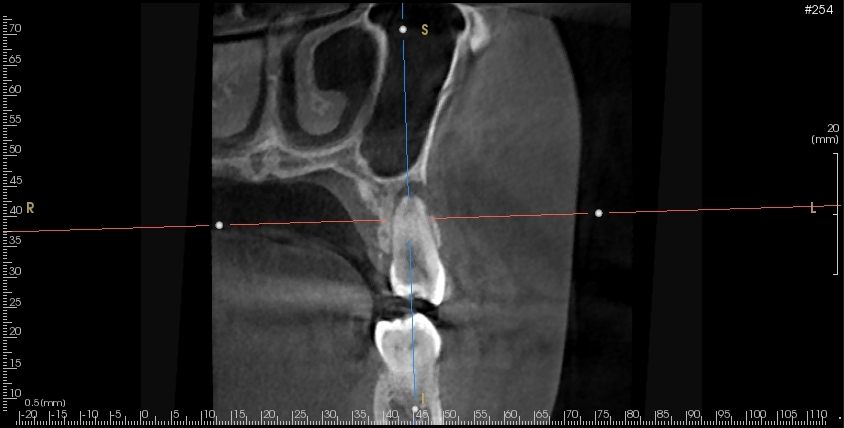

まず再生歯内療法(REGENERATIVE ENDODONTICS)とは、何かというと歯髄壊死と診断された根未完成の歯に行われる治療です。

この治療の目的は歯髄象牙質複合体を再生し、歯の寿命を伸ばし、正常な機能を回復することです。

この治療は根未完成歯に限られますが、失活した根未完成歯に対して、神経を全て除去することなく正常な機能に戻すことができる可能性がある治療です。